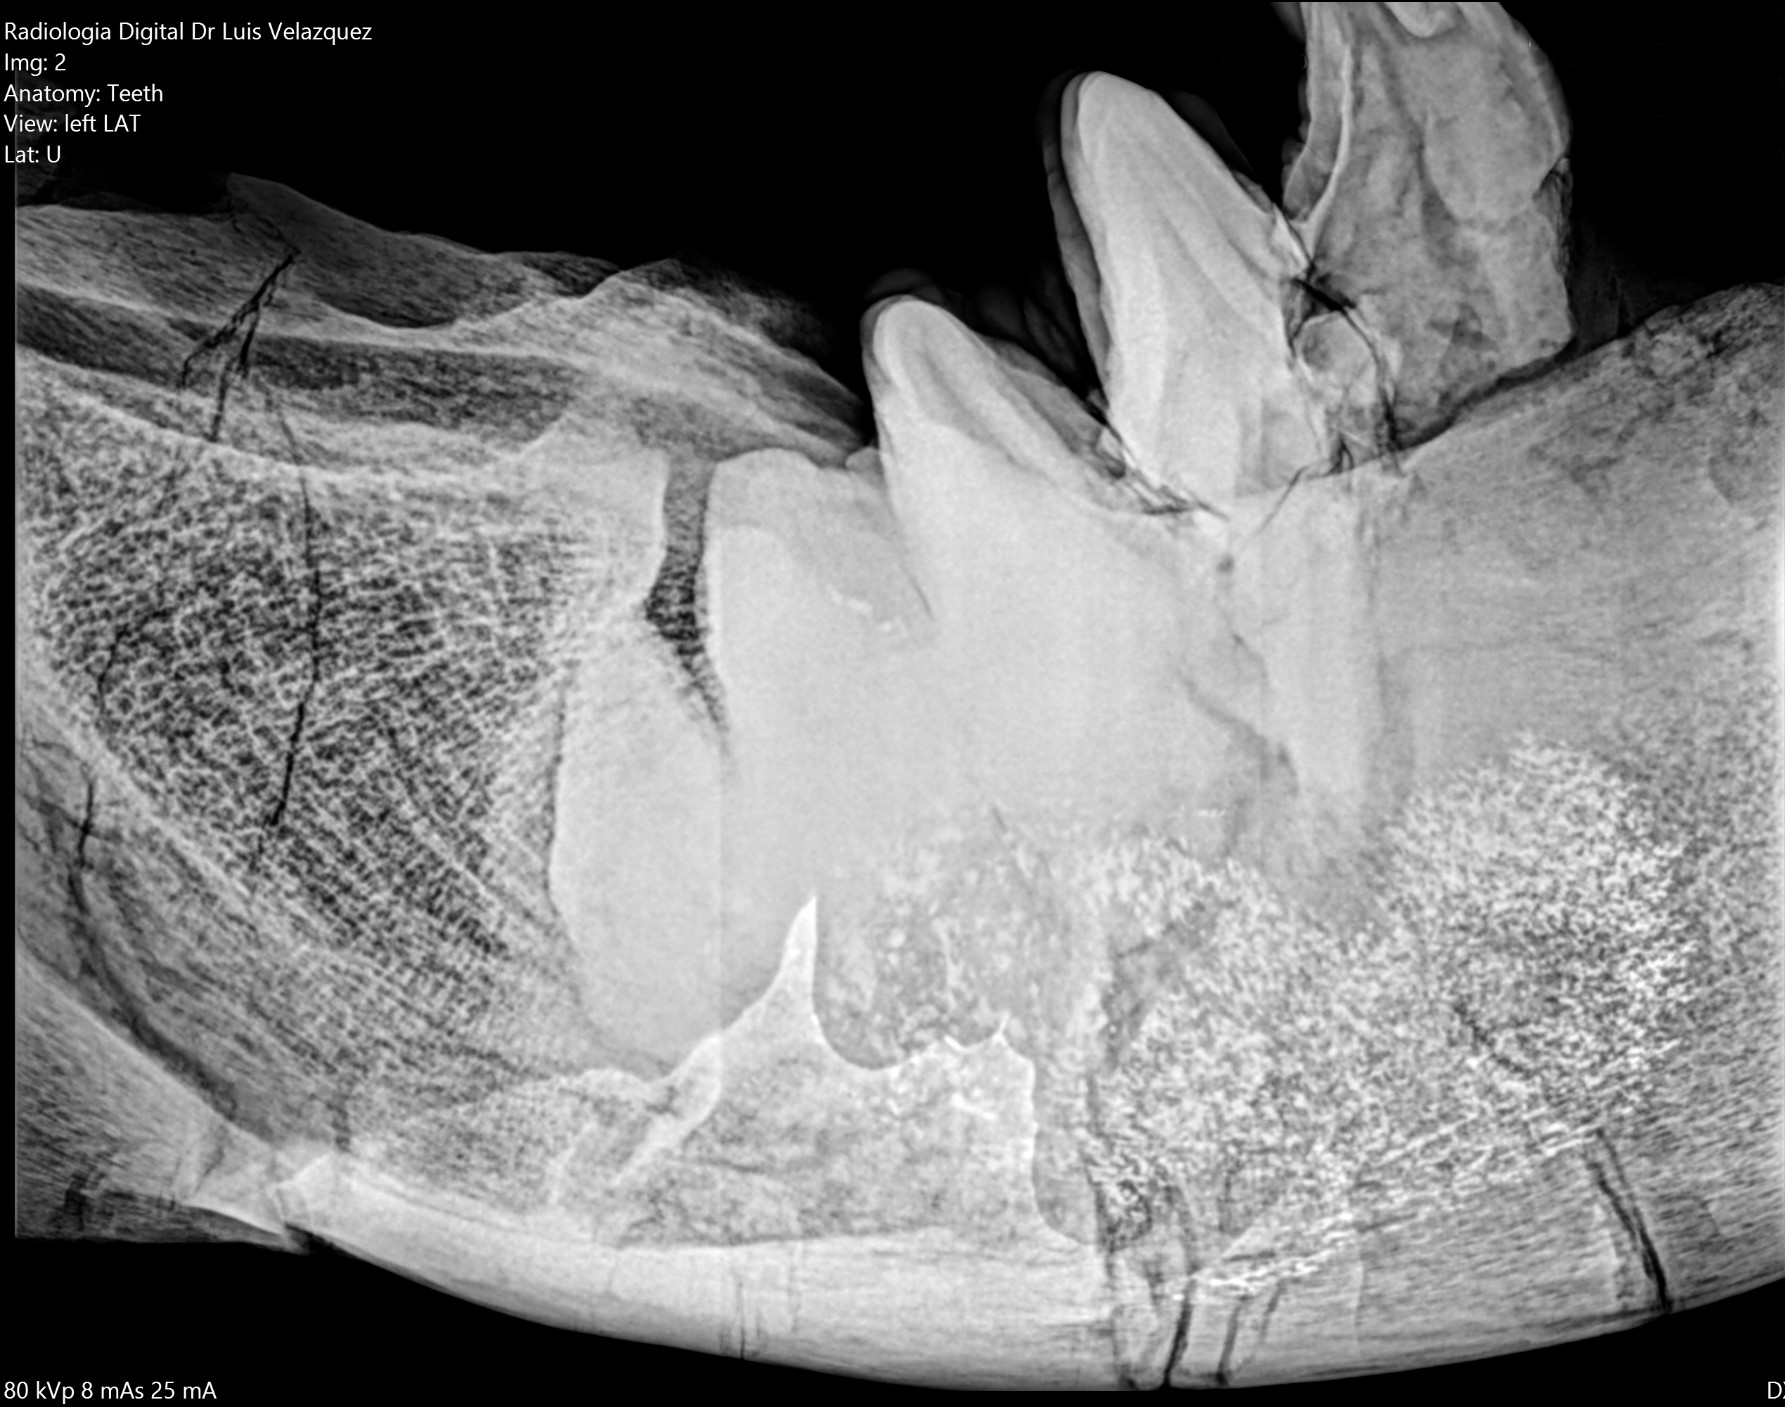

Radiología Digital como Herramienta Complementaria en el Dictamen de Bienes Muebles

Desde el descubrimiento de los rayos “X” y las placas radiográficas por Wilhelm Conrad Roentgen y su posterior difusión a través de la Asociación Físico médica de Wurzburg el 28 de diciembre de 1895, que fue la primera asociación que habló de los nuevos rayos que podían penetrar el cuerpo y fotografiar los huesos, ha habido muchos cambios tanto en la forma de obtener, procesar e incluso en la forma de visualizar, manejar y almacenar las placas radiográficas.